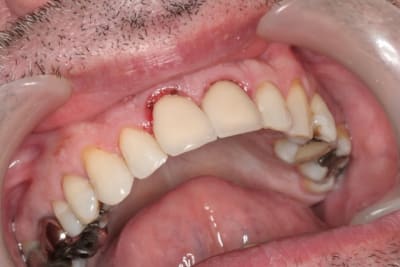

juste pour illustrer mon propos....

ici une MCI ou plutôt, devrais je dire une vis de cica anatomique immédiate.